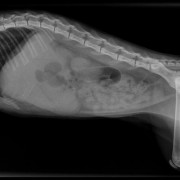

Snuf wordt verdoofd en de dierenarts opent de buik

De blaas wordt opgezocht en geopend

En daar is de eerste steen...

Close up

De boosdoeners